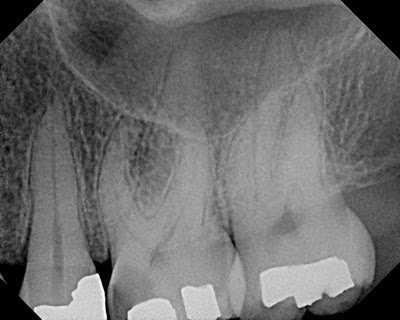

This patient presented with mesial decay on #14 causing discomfort. The tooth was normal to percussion, probing and no response to thermal test. DX: Necrotic pulp w/ normal periapex. A crack was noted on the distal marginal ridge. RCT recommended.

Closer examination finds that the crack ends near the level of the CEJ. Pt is informed of the crack and the prognosis is good, since the new crown will be able to cover the crack. The crack should be removed at the time of the build-up.